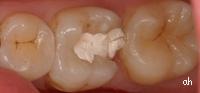

anicenne obturation en composite

fraisage léger de la dent

le nouveau composite en place